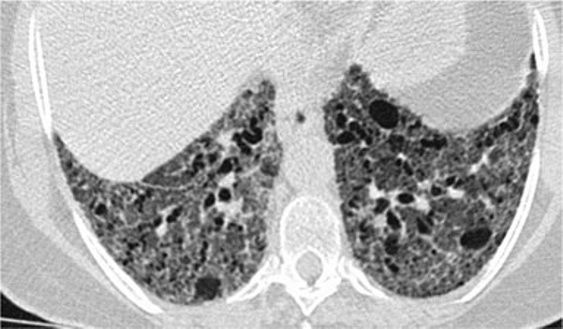

8、囊性病变

囊性模式由界限分明,圆形和外接空气的实质组成,有界限分明的壁和与正常肺。

经典疾病:淋巴管平滑肌肌瘤病(LAM),其特征是通常存在圆形的薄壁肺囊肿,没有在局部明显的特点,分布广泛,包括肋骨角和肺底。 LAM可能伴有胸水表现为胸膜胸腔积液。鉴别诊断是随机分布的囊肿,临床病史表现几乎只影响着育龄妇女。鉴别疾病:是肺组织细胞增生症、淋巴细胞性间质性肺炎(LIP)和小叶性肺气肿。

*LAM。上叶水平的HRCT表现出“囊性模式”,其特征是位于肺实质和隔中的许多大小不等的薄壁“真”囊腔的存在。